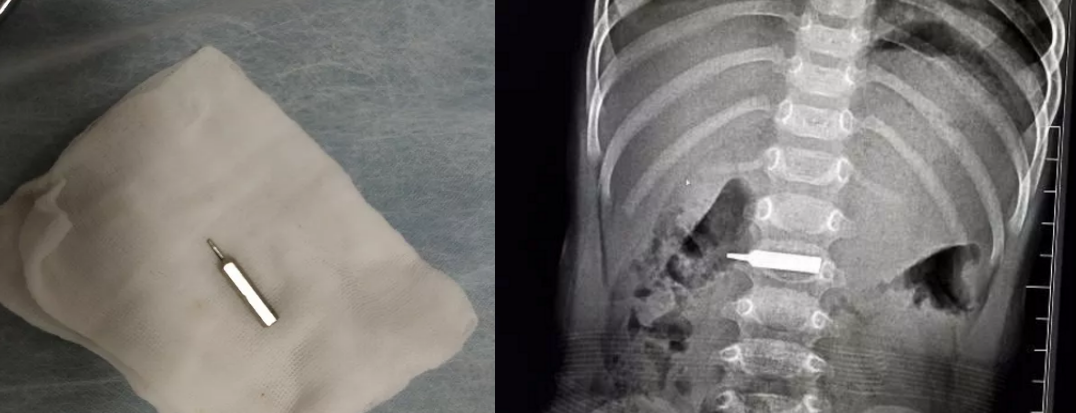

男宝误吞螺丝刀头,随时可能肠穿孔。

“太惊险了,手术前,这个螺丝刀头一半在胃里,一半已经进入十二指肠,晚一步后果不堪设想。”边鹏介绍,手术还是有很大难度,鹏鹏胃里当时都是食物残渣,手术第一步就是将异物拽回到胃里,这个过程中,异物直接就掉进食物残渣里。”我们先对孩子的胃进行清理,然后才将异物取出。” 边鹏说,手术全程2个小时,很顺利,经过测量,发现异物长约3厘米左右,鹏鹏今天可以喝水了,也可以少量的进食些米汤,明后天就可以办理出院了。